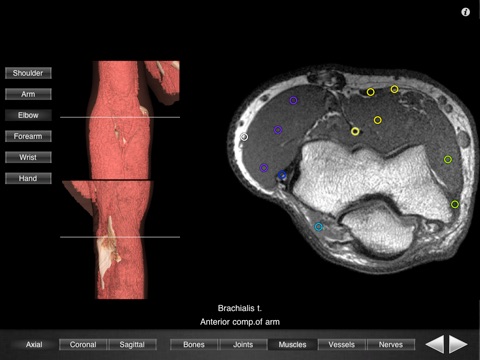

Monster Anatomy – Upper Limb is the complement of Monster Anatomy HD – Lower Limb and is compatible with iPhone and iPad. This application is designed for healthcare professionals (Radiologists, General Practitioners, Orthopedists, Surgeons, Physiotherapists among others) as well for students, as a reference and learning tool. It contains 502 contiguous MR slices (2-4 mm thickness) in the three anatomical planes.

- Over 500 different labels in accordance with the “Terminologia Anatomica" and current literature references.

- Over 16.000 tags.

- The five different display modes available (bones, joints, muscles, blood vessels and nerves) facilitates label visualization. - High image quality with a zooming tool.